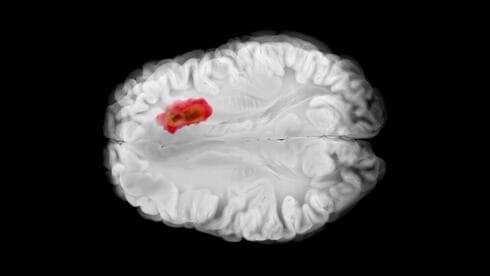

תא חיידק (מאורך, במרכז התמונה) בתוך תא של סרטן מוח מסוג גליובלסטומה, כפי שנראה מבעד למיקרוסקופ אלקטרונים. הנקודות השחורות בתא החיידק - נוגדנים מהונדסים שנושאים חלקיקי זהב ונקשרים באופן ממוקד לרכיב הקיים רק במעטפת התא של חיידקים ולא בתאים אנושיים